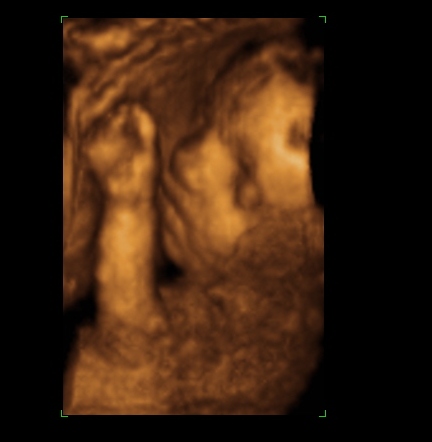

A második képen nyitva van a szeme is